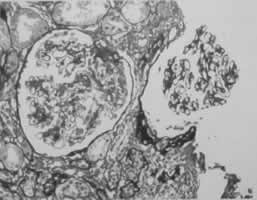

肺表面瀰漫性出血,切面可見水腫和陳舊的出血。鏡檢見肺泡內出血,肺泡腔內常有吞噬含鐵血黃素的吞噬細胞,局灶性肺泡纖維組織增殖。免疫螢光檢查顯示肺泡間隔和肺毛細血管基膜有免疫球蛋白和C3呈線狀沉積,腎臟病理改變似急進性腎小球腎炎。此外,早期腎小球毛細血管呈局灶和節段性壞死,後期腎小球周圍有淋巴細胞浸潤為一特點。